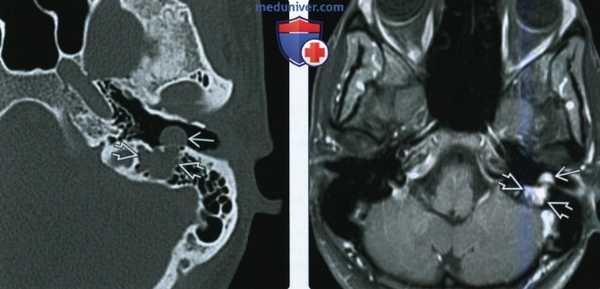

При проведении диффузионно-тензорной трактографии реконструированы каудальная группа нервов и кортикоспинальный тракт. Последний компримирован опухолью и оттеснен влево. На нижнем полюсе располагались корешки верхних шейных сегментов спинного мозга и подъязычного нерва. Языкоглоточный и блуждающий нерв располагались на верхнем полюсе опухоли и были деформированы (рис. 3). Рис. 3. Диффузионно-тензорная трактография головного мозга пациентки В. до операции. Определен кортикоспинальный тракт в стволе головного мозга, на верхнем полюсе опухоли располагаются языкоглоточный и блуждающий нервы, по переднему полюсу проходят добавочный нерв и корешок СI. а — кортикоспинальный тракт, б — корешки IX, X, XI черепно-мозговых нервов, в — акустико-фациальная группа нервов, г — опухоль.

2. КТ при шванноме подъязычного нерва:

• КТ без контрастного усиления:

о Четко отграниченное объемное образование мягкотканной плотности по ходу ЧН XII

о В ипсилатеральной половине языка вследствие денервационной атрофии наблюдается коэффициент ослабления, соответствующий жировой ткани

• КТ с КУ:

о Однородное контрастирование ± интрамуральные кисты

• КТ в костном окне:

о Гладкостенный четко отграниченный расширенный КПН

о Корональная: увеличение размеров, перестройка нижней поверхности яремного бугорка (ниже «орлиного клюва»)